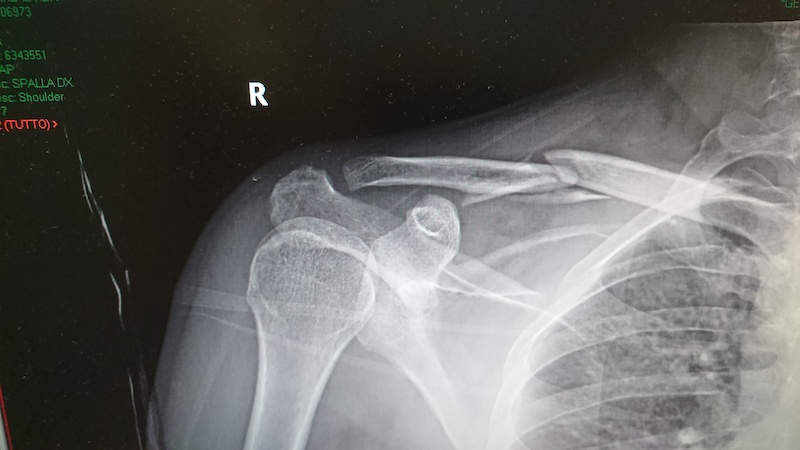

11+ Broken Shoulder Bone Xray PNG. Broken clavicle bone, shoulder medical xray. This video describes the basics of shoulder joint x ray, brief anatomy of the shoulder joint, how to read a shoulder x ray, various standard views and their importance (shoulder pain, shoulder dislocation and fracture).

New bone growth around a break considered a good sign that the bone fragments are reuniting. Broken clavicle bone fixation, fracture repair. With your doctor's guidance, you may commence shoulder movement as the fracture. Scapular fractures occur more often in young men broken shoulder blades are often caused by heavy forces that might also include severe injuries to the chest, lungs, and internal organs.